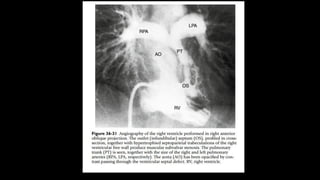

• 4. Anomalous coronary artery distribution can be

imaged accurately by echocardiographic

studies (Fig. 14-21). The major concern is to rule

out any branch of the coronary artery

crossing the RVOT. Thus, preoperative cardiac

catheterization solely for the diagnosis

of coronary artery anatomy is not necessary.

• Figure 4: Origin of the LAD from the RCA crossing the right

ventricular outflow tract. (a) High parasternal short-axis view.

The enlarged proximal RCA supplies the LAD. (b) Leftward

angled parasternal long-axis view profiling the right ventricular

outflow tract (infundibulum) free wall. The LAD is seen in cross-

section approximately 7 mm below the pulmonary valve[25] and

52-year-old male, status post TOF repair. (c) Anomalous origin

of the LAD from the right coronary cusp (arrowhead). (d) The

anomalous LAD courses anterior to the RVOT (arrows).

(reproduced with permission from Kapur S, Aeron G, Vojta CN.

Pictorial review of coronary anomalies in Tetralogy of Fallot. J

Cardiovasc Comput Tomogr. 2015 Nov-Dec; 9(6):593-6.). A:

Anterior, AoV: Aortic valve, Inf: Infundibulum, L: Left, LAD: Left

anterior descending coronary artery, MPA: Main pulmonary

artery, RCA: Right coronary artery, R/S: Right/superior, RVOT:

Right ventricular outflow tract